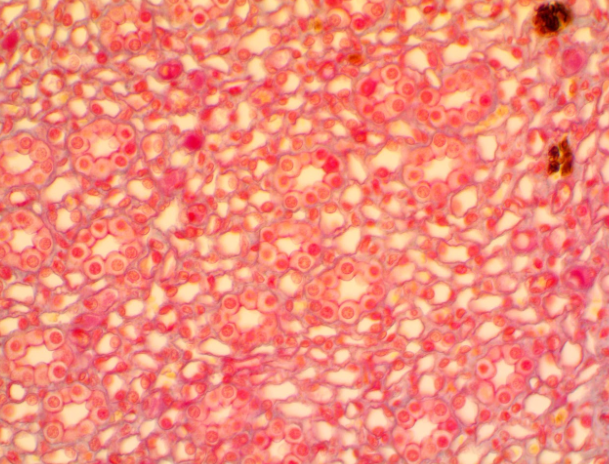

What is this

Blood Connective Tissue